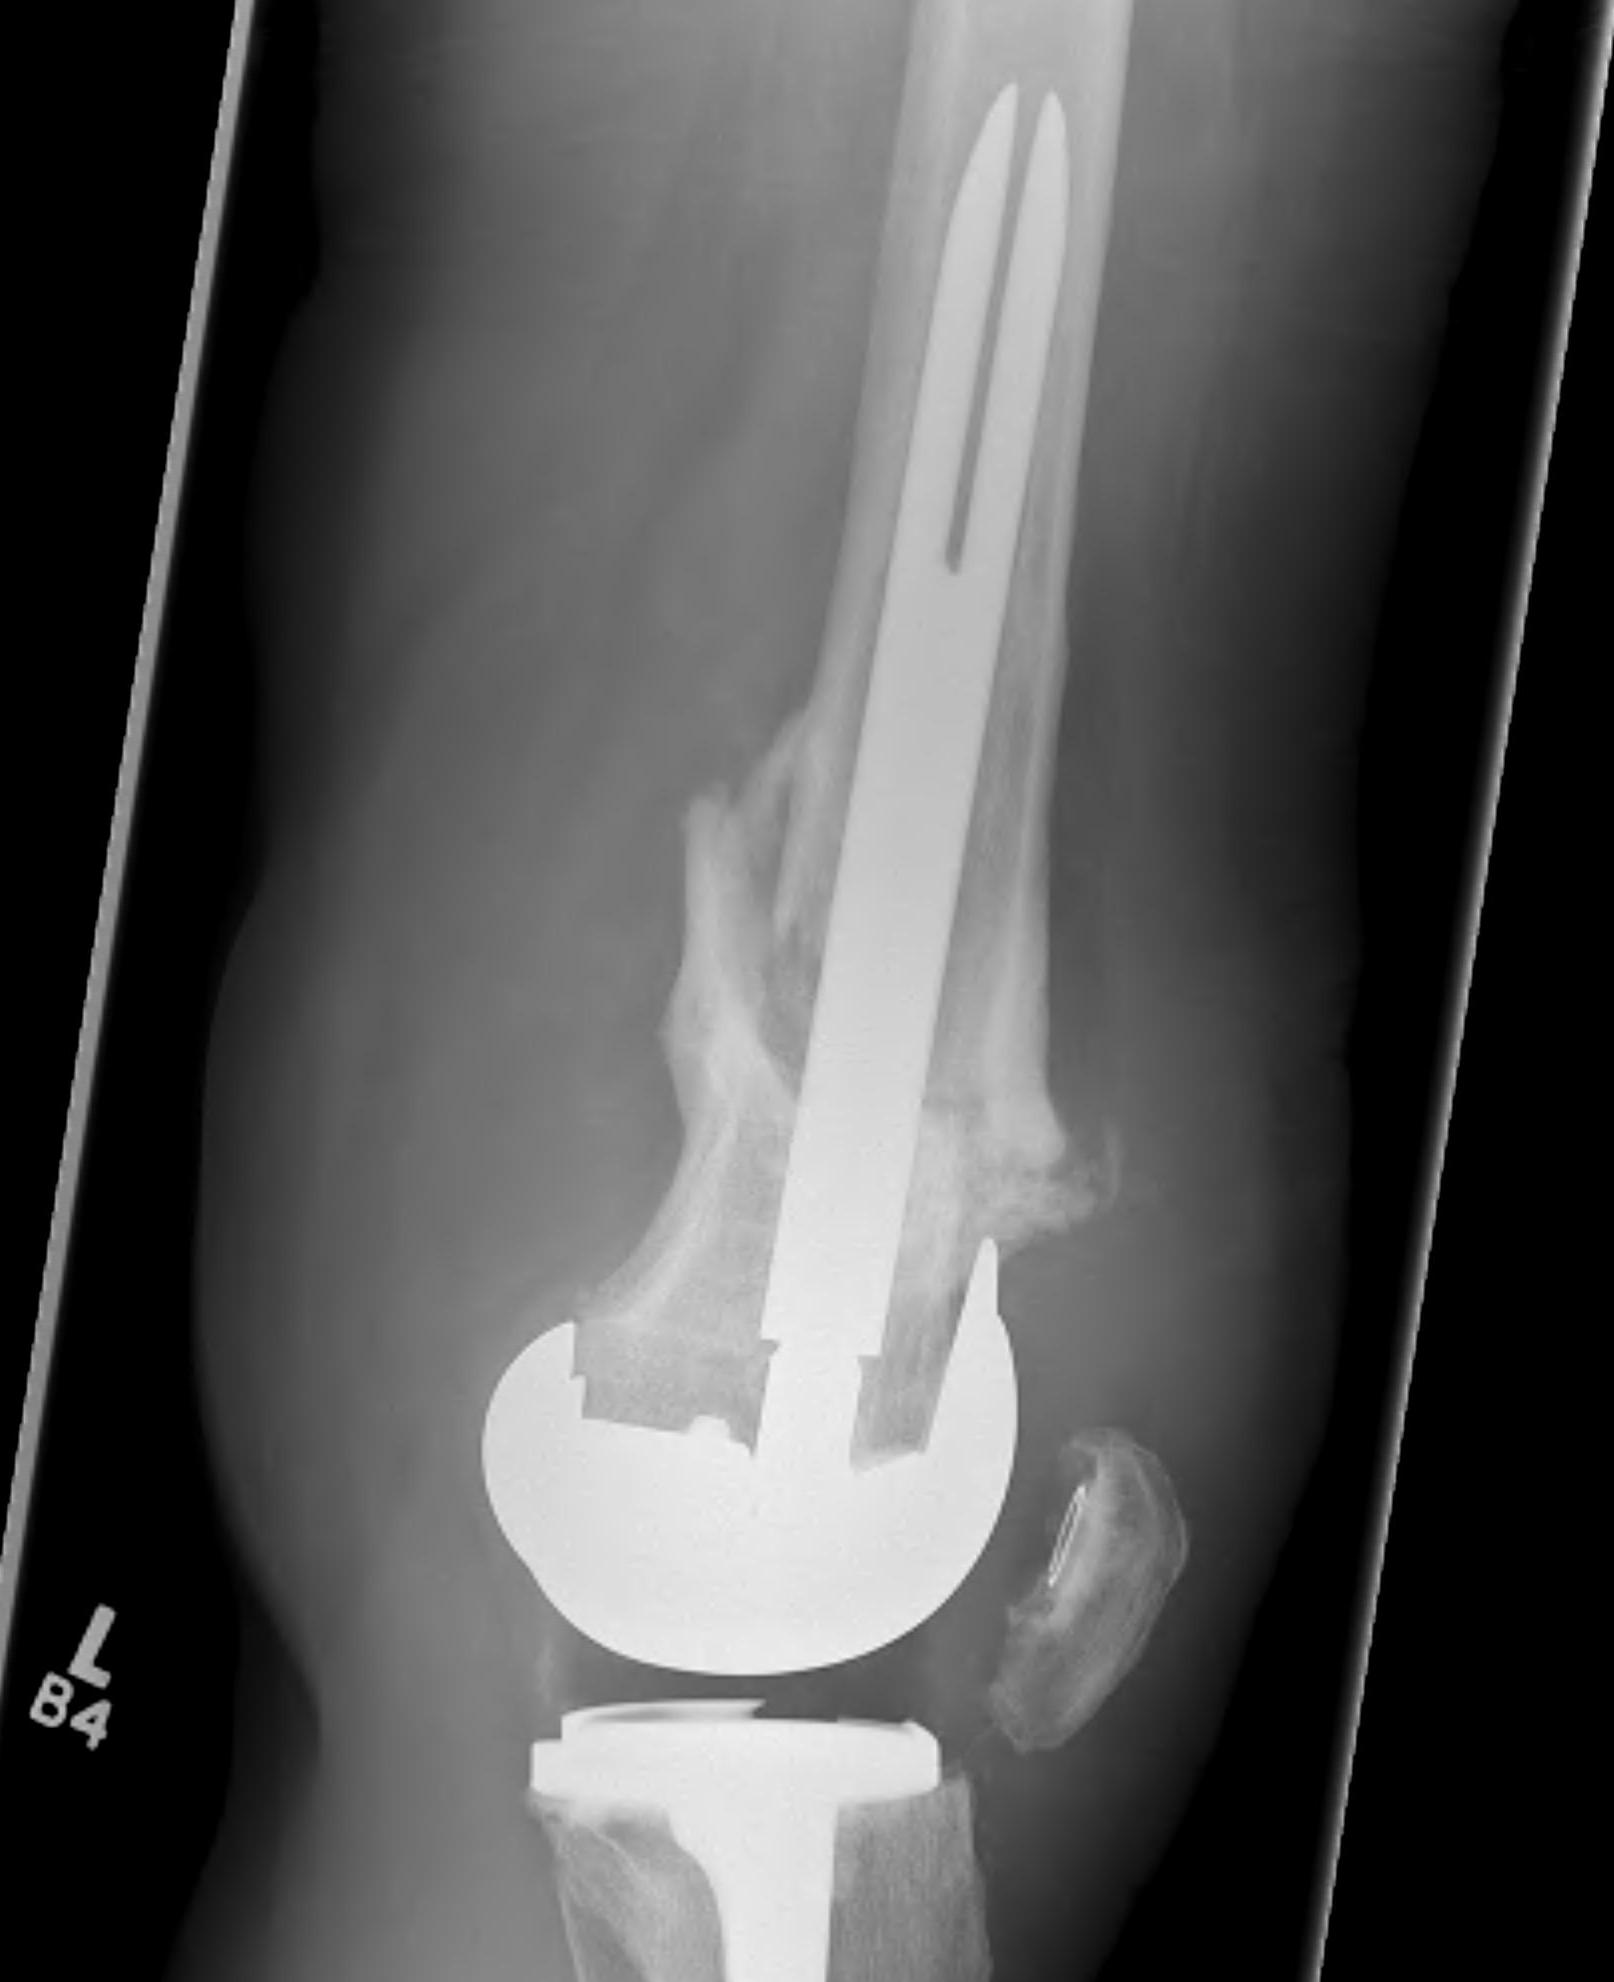

Distal Femoral Replacement

Indications

Elderly osteoporotic patient

Unreconstructable distal femur

Multiple co-morbidities

Difficulty non weight bearing

Results

Hart et al. J Arthroplasty 2017

- ORIF v distal femoral replacement in patients > 70 years old

- reoperation rate 10% in both groups

- 20% non union in ORIF

- at one year, 1/4 ORIF patients wheelchair bound, all DFR patients ambulatory

- AOANJRR review of DFR in native knees

- 10% revision rate at 3y

- most commonly loosening > infection